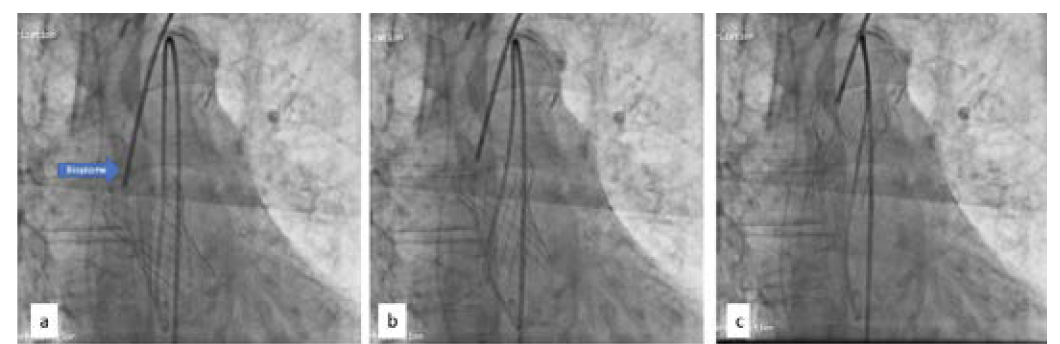

In view of significant stenosis of the lower limb arteries, the patient was prepared for TAVR through a subclavian approach. An 18 Fr DrySeal sheath (Gore Medical) was placed, and a gradient of 76 mm Hg was measured across the aortic valve. Over a Confida Brecker guidewire (Medtronic), a 26-mm Evolut R self-expanding valve (Medtronic) was taken across the aortic valve. Rapid right ventricular pacing was initiated at 180 beats per minute, and the valve was deployed below the aortic annulus (Figure 3a). A chunk of calcium near the noncoronary sinus did not allow the valve to expand (Figure 3b), and immediately after deployment the valve popped out into the ascending aorta (Figure 3c).

There was no coronary obstruction, and the patient was hemodynamically stable. Using a bioptome (Cordis), the valve was pulled high in the aorta, leaving it just proximal to the origin of the brachiocephalic artery (Figure 4). The aortic valve was recrossed and another 26-mm Evolut R self-expanding valve was deployed successfully (Figure 5).